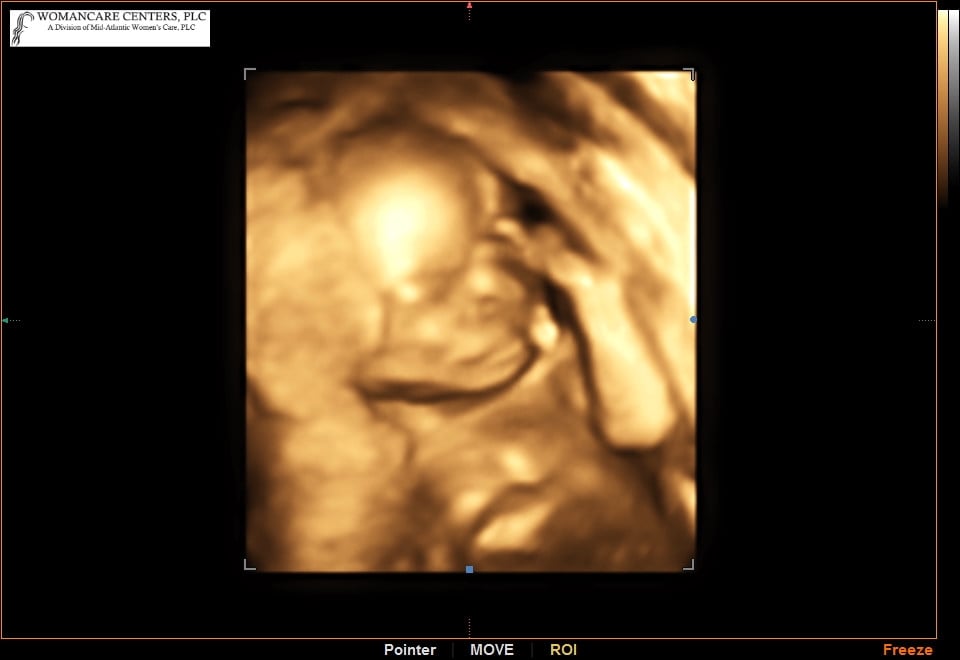

Here's our tiny one from our 20 week anatomy scan yesterday! Found out she's a girl! Side note - our NT scan also provided us with a 3D image but it didn't yet look human. Happy to say she is looking more like a baby now!

Side note - our NT scan also provided us with a 3D image but it didn't yet look human. Happy to say she is looking more like a baby now!